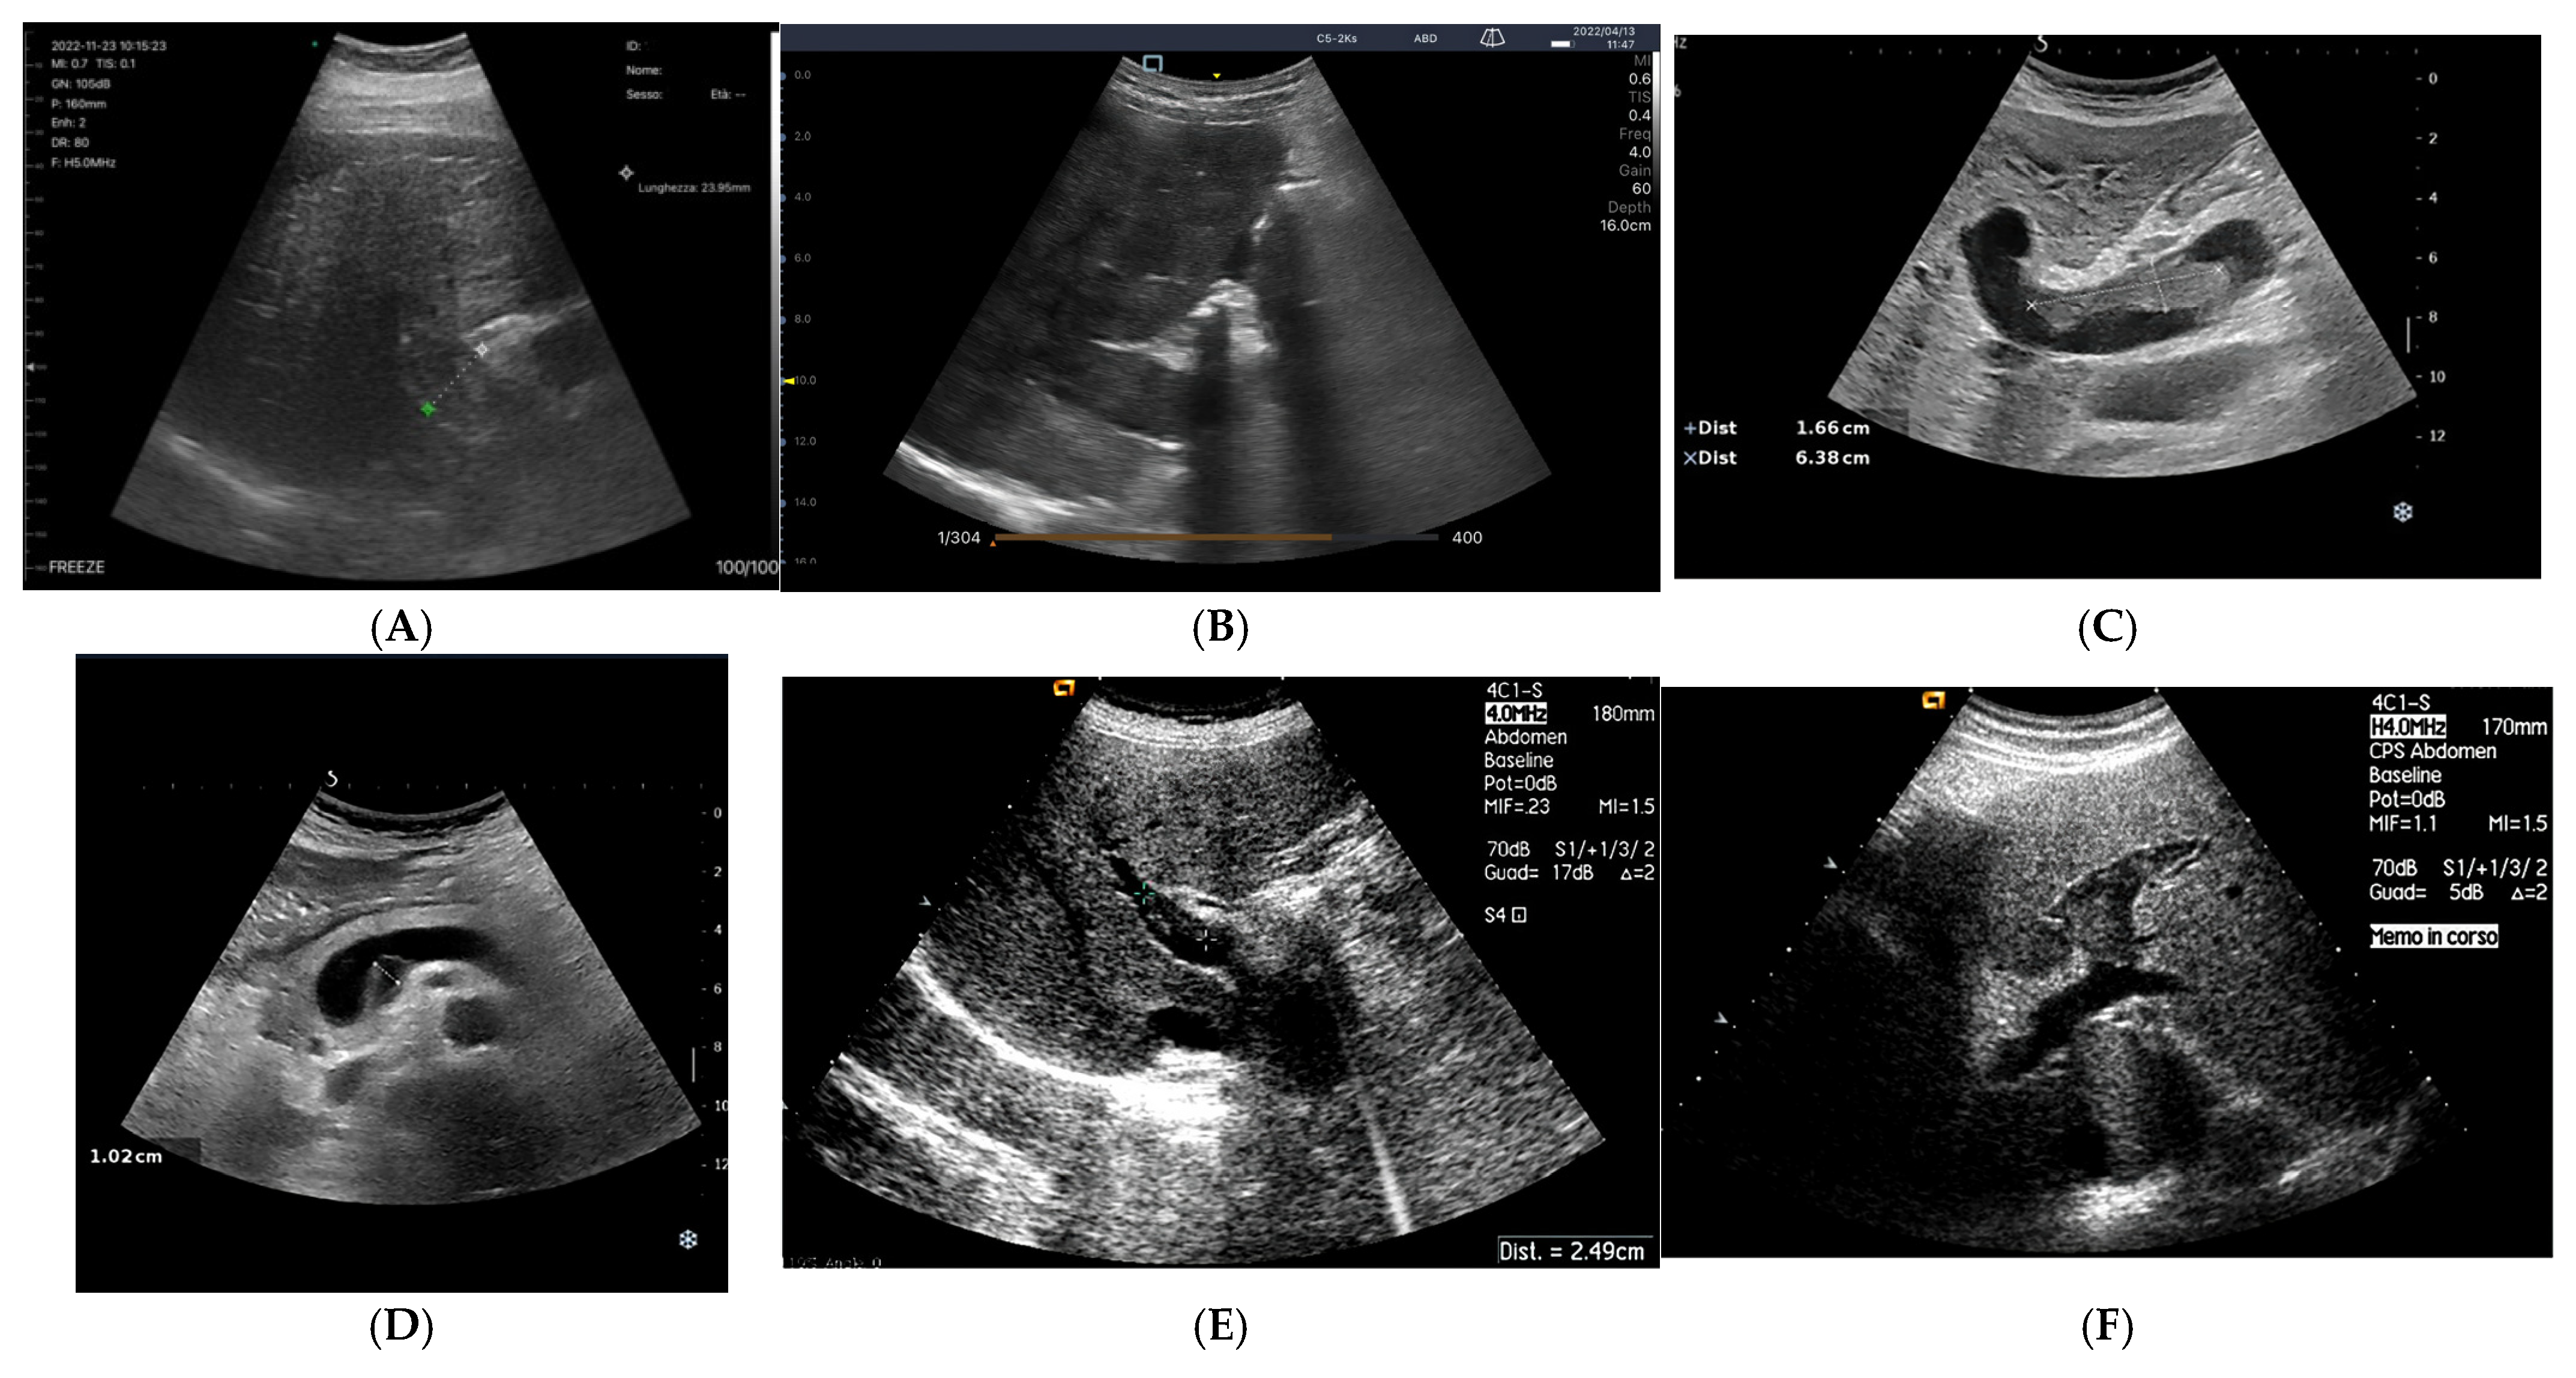

- Grading Venous Congestion: Venous congestion is categorized into grades 0–3 based on waveform alterations, a system known as VExUS (Venous Excess Ultrasound Score) (Figure 14) [63]. This grading system provides a practical method for assessing the severity of venous congestion in clinical settings (Figure 15).

- Intra-Renal Vein Doppler: Similar to the portal vein, intra-renal veins show continuous flow under normal conditions, but congestion leads to a pulsatile pattern. This can manifest as a biphasic pattern in moderate congestion and a monophasic pattern in severe cases [114]. Altered intra-renal flow is associated with poor outcomes in heart failure and pulmonary hypertension patients [56,114].

- Portal Vein Doppler: Normal portal vein flow is continuous, but severe venous congestion can cause pulsatility in the portal circulation. The pulsatility fraction (PVPF: [(Vmax − Vmin)/Vmax] × 100) quantifies this, with values above 30% indicating mild abnormalities and above 50% suggesting severe congestion [57]. Elevated PVPF is a strong predictor of acute kidney injury in post-cardiac surgery patients.

- Hepatic Vein Doppler: In normal conditions, hepatic vein (HV) flow is pulsatile, corresponding to the RAP waveform. Pathologies like right ventricular dysfunction or tricuspid regurgitation can alter HV waveforms, and increasing RAP can reduce venous return during systole, leading to distinct changes in the waveform.